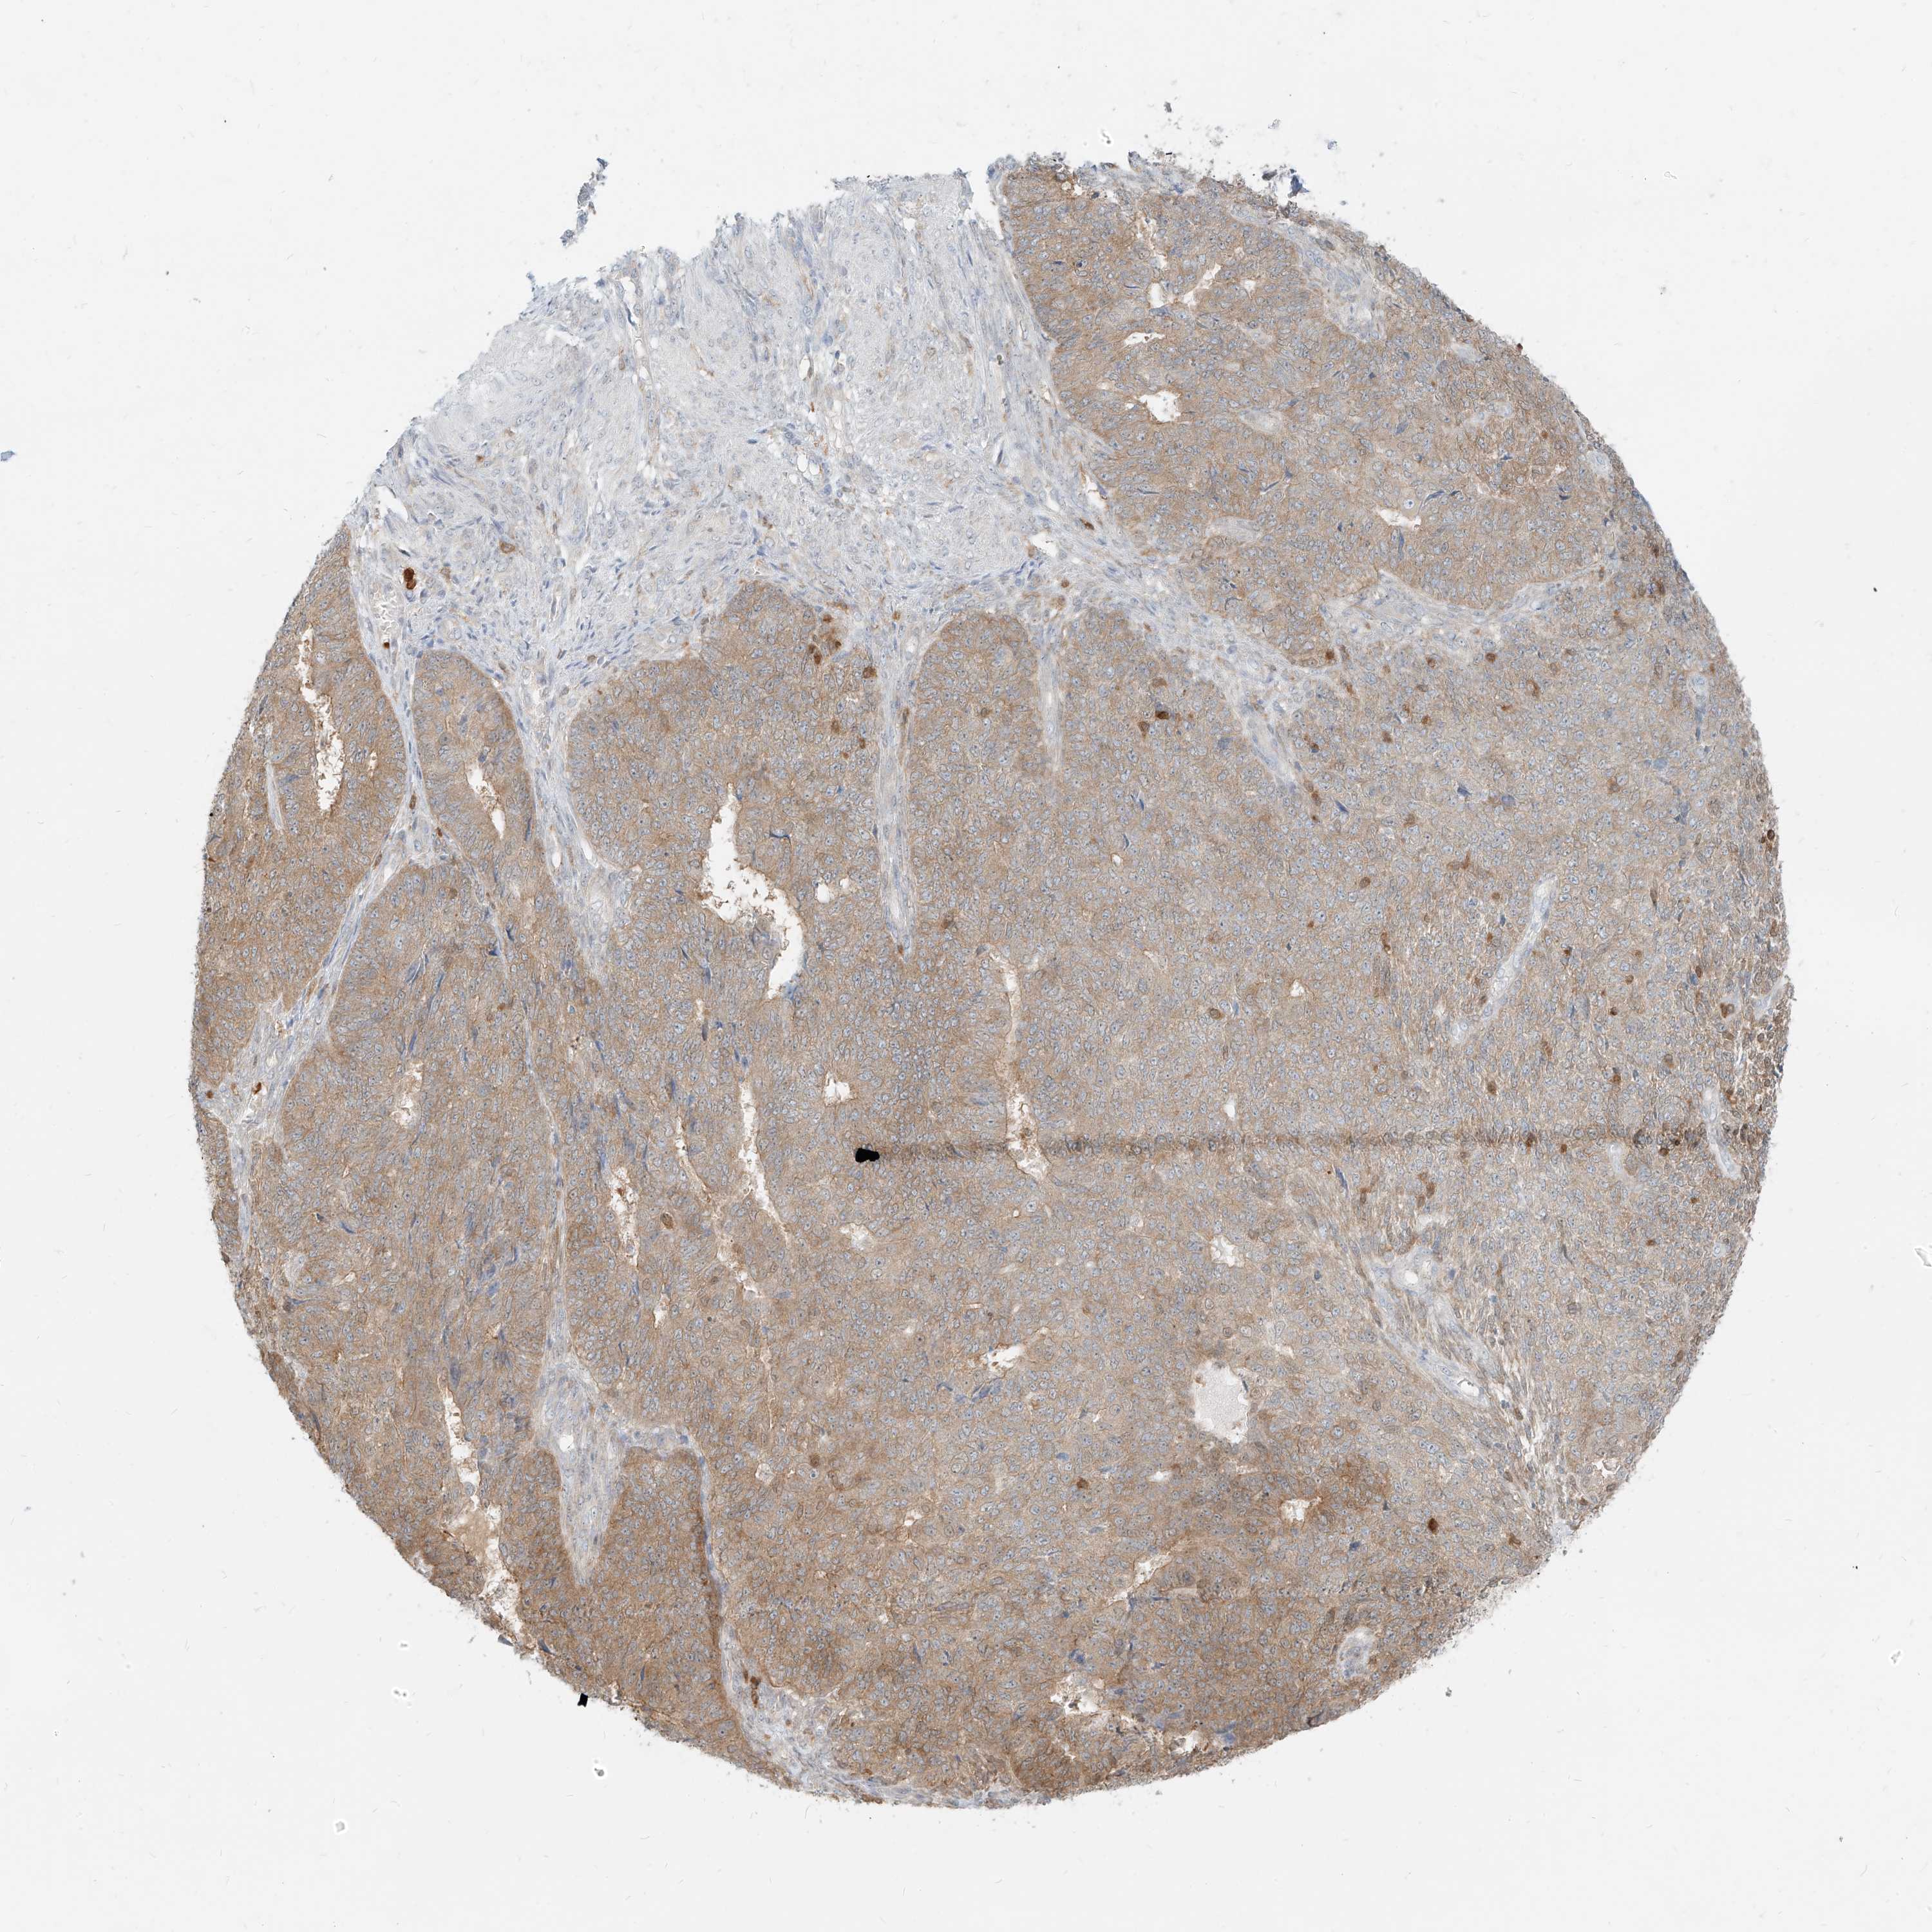

ENDOMETRIAL CANCER - Protein expressioni

A mouse-over function shows sample information and annotation data. Click on an image to view it in a full screen mode. Samples can be filtered based on level of antibody staining by selecting one or several of the following categories: high, medium, low and not detected. The assay and annotation is described here.

Note that samples used for immunohistochemistry by the Human Protein Atlas do not correspond to samples in the TCGA dataset.

Antibody stainingi

Antibody staining in the annotated cell types in the current human tissue is reported as not detected, low, medium, or high, based on conventional immunohistochemistry profiling in selected tissues. This score is based on the combination of the staining intensity and fraction of stained cells.

Each image is clickable and will lead to virtual microscopy that enables deeper exploration of all samples and also displays staining intensity scores, fraction scores and subcellular localization as well as patient and tissue information for each sample.

Antibody HPA031314

Antibody HPA031315

Staining

High

Medium

Low

Not detected

Intensity

Strong

Moderate

Weak

Negative

Quantity

>75%

75%-25%

<25%

None

Location

Nuclear

Cytoplasmic/membranous

Cytoplasmic/membranous,nuclear

Adenocarcinoma, metastatic, NOS